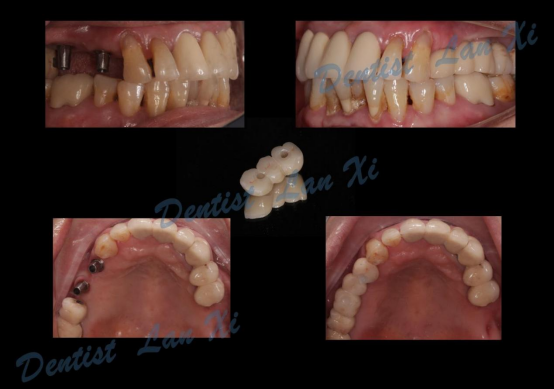

第六步:最终修复

一、以终为始 更精准

在数字化种植导板下,通过CBCT、口扫等途径获取口腔三维信息内容。使患者在种植之前就可以了解到种植方案的相关细节,清晰地看到牙齿修复之后的模拟展示图,提前预知种植术后的效果。

二、精准控制 更安全

在数字化种植导板下的外科手术更加精准。种植体植入方向、位置、角度、深度等一目了然,即可将种植体精准植入到最佳位置,获得更优异的临床效果,手术安全性更高。